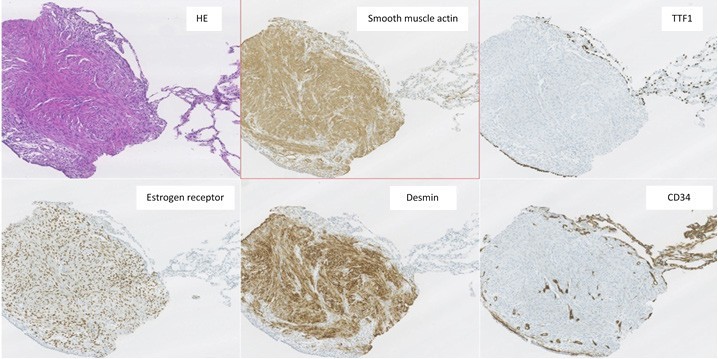

Immunohistochemical staining showed positivity for smooth-muscle actin, desmin and estrogen and progesterone receptors, while showing negativity for TTF1, AE1/AE3, bcl2 and CD34. The histological findings were compatible with BML (Figure 3). Due to these findings, the patient (who had no clinical history of known leiomyomas or other gynecological conditions) was referred to gynecological consultation and transvaginal ultrasound examination revealed a heterogeneous uterine wall with two intramural hypoechoic lesions (measuring 12 x 12 mm and 10 x 6 mm) and one subserosal hypoechoic lesion (measuring 54 x 28 mm), suggestive of uterine leiomyomas (Figure 4). The patient underwent hysterectomy and bilateral adnexectomy, and surgical histopathological study confirmed the diagnosis of multiple uterine leiomyomas, confirming the origin of the BML lesions found in the lungs. The latest postoperative CT chest scan for lung nodules evaluation showed overlapping characteristics, compared to previous imaging studies. As such, these BML lesions remain morphologically and numerically stable. The patient remained asymptomatic and was followed- up in consultation. No surgical or hormonal therapy was performed in regard to BML, and a CT chest scan was scheduled 6 months later to monitor the lesions.

Figure 3: Pathological findings of transthoracic lung biopsy of the 9 mm cavitary nodule revealed, by H&E staining, pulmonary parenchyma with mostly preserved alveolar structure, partially occupied by spindle smooth cell proliferation, without pleomorphism, necrotic areas, atypia or mitotic figures. Immunohistochemical staining showed positivity for smooth-muscle actin, desmin and estrogen and progesterone receptors, while showing negativity for TTF1, AE1/AE3, bcl2 and CD34. These histological findings were compatible with BML.